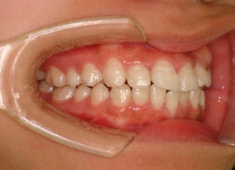

治療前